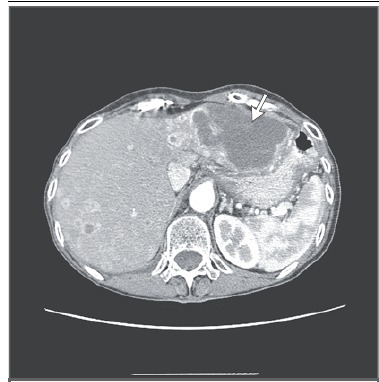

研究病例发现,定义原发灶不明的转移癌的组织来源既带来了希望也提出了挑战(图 3 和图 4)。免疫组化结果能够确定肿瘤来源的患者约占所有原发灶不明的转移癌患者的 25%。例如甲状腺转录因子 1(TTF1)阳性,细胞角蛋白 7(CK7)阳性提示肺癌来源,细胞角蛋白 20 阳性,同源蛋白 CDX-2 阳性和 CK7 阴性提示消化道肿瘤来源,GCDFP ( 多囊肿疾病流体蛋白)-15 阳性或乳腺珠蛋白阳性,CK7 阳性提示乳腺癌来源。一般来说,肿瘤的播散类型支持免疫组化的结果,有时,免疫组化的结果与影像学检查不一致(图 3A 和 3B)。

图 3 评价原发灶不明的转移癌时影像学发现与免疫组化结果不一致患者 77 岁,女性,无吸烟史,肺炎随访时胸部发现肺右上叶一 5.7 厘米的肿块,侵及右中叶和裂隙(图 A,箭头)。取肿块活检发现中分化腺癌,伴同源蛋白质 CDX-2,CK20,癌胚抗原强阳性,CK7 和 TTF1 阴性。病理报告结果提示下消化道肿瘤来源,包括阑尾和结直肠。上消化道内镜检查和结肠镜检查均未见异常。无明确证据提示小肠和阑尾肿瘤来源。术前短期氟尿嘧啶和奥沙利铂化疗后,患者手术切除肺部肿块(图 B,箭头)。术后病理报告结果不变(假设结直肠癌转移),术后按原方案化疗。术后结肠镜检查结果阴性。患者入组微小 RNA 组织来源分子分析临床试验证实结肠肿瘤来源。尽管化疗能否使该类患者获益还未知,临床医生制定治疗方案时应考虑病理结果。结肠癌来源原发灶不明的转移癌最常表现为孤立转移和卵巢转移。